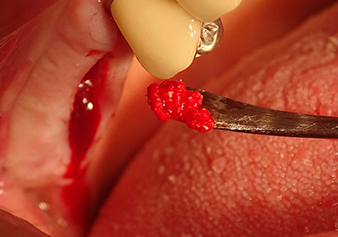

Implant bed preparation and augmentation

Following an intermediate check (Fig. 4) a further preparation step was performed (Fig. 5). Afterwards, the hydraulic Z35P instrument was used to lift the membrane to the desired position (Fig. 6 and 7). This was followed by further piezosurgical preparation of the implant bed, concluded with a rotary bur and shoulder milling cutter up to the implant diameter of 4.8 mm. Before the implant was inserted, the augmentation material (particle size approx. 0.8-1.6 mm) was introduced underneath the Schneiderian membrane (Fig. 8).